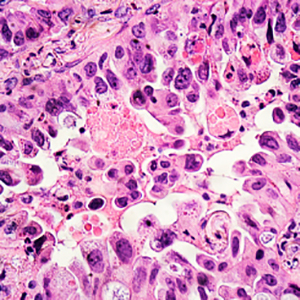

Background: Chronic obstructive pulmonary disease (COPD) is a condition resulting from a persistent inflammatory state in the airways even after smoking cessation. Intriguingly, the reasons behind this persistence of the inflammatory influx without smoking exposure have not been fully unraveled. We aimed to explore the hypothesis that systemic inflammation in COPD patients influences lung cell inflammatory response.

Methods: We cultured human lung fibroblast and human airway epithelial cell lines with plasma from COPD patients (four emphysematous-COPD, four asthma-COPD overlap, four chronic bronchitis-COPD, and four bronchiectasis-COPD), and four smokers or ex-smokers without COPD as controls. We measured Interleukine-8 (IL-8), C-reactive protein (CRP) and matrix metalloproteinase-9 (MMP-9) in plasma and culture supernatants by ELISA.

Results: Cells stimulated with plasma from COPD patients and control subjects produced higher CRP, IL-8 and MMP-9 levels, an increase for COPD in CRP(p=0.039) in epithelial cells and IL-8(p=0.039) in fibroblasts and decrease for MMP-9(p=0.039) in fibroblasts. The response was higher in epithelial cells for IL-8(p=0.003) and in fibroblasts for MMP-9(p=0.063). The plasma from chronic bronchitis and bronchiectasis phenotypes induced higher IL-8 in fibroblasts.

Conclusions: Plasma from COPD patients increases the inflammatory response in lung epithelial cells and lung fibroblasts, with a different response depending on the cell type and clinical phenotype.